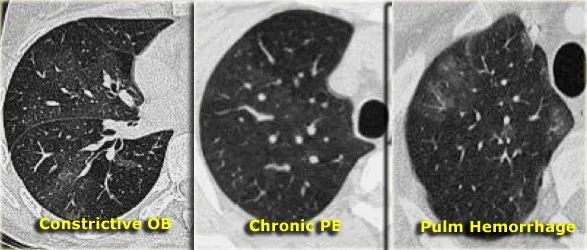

马赛克密度的三种不同原因

很难区分这三个实体。有两个进一步鉴别的诊断提示:

如果与“白色”肺相比,在“黑色”肺中很难看到肺血管,那么“黑色”肺很可能是不正常的。

然后有两种可能:阻塞性毛细支气管炎(上图左)或慢性肺栓塞(上图中)。

有时,这些可以通过呼气扫描来区分。

如果血管在‘黑’肺和‘白’肺中是相同的,那么可能是一个浸润性肺部病变,就像上图右边那个有肺出血的病人。